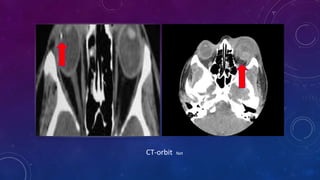

INVESTIGATIONS

1.B - scan ultrasonography

2.Plain orbital x-ray

3.CT-scan

Vitreous Hemorrhage and RD Net

Orbital plain x-ray Net

CT-orbit Net